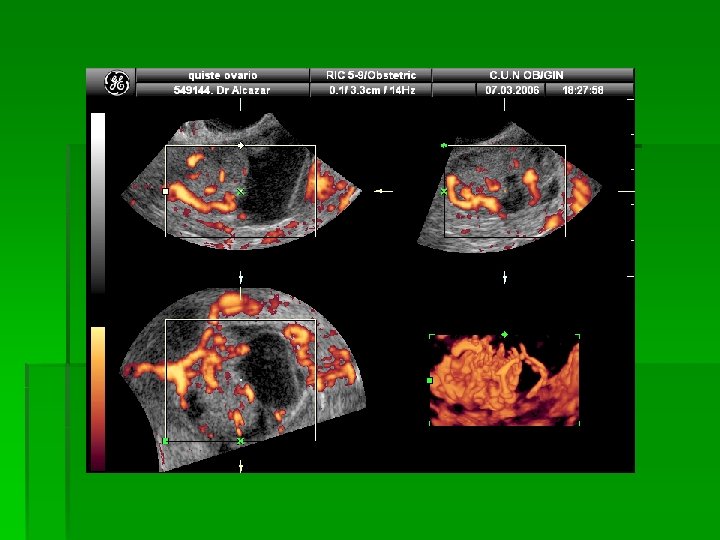

PROBIR OVARIJSKOG KARCINOMA v. UZV: v 2 D, CD, PD, 3 DPD, 3 DPDA v 3 D-PDA- vascular sampling (Alcazar JL)

UZV v BENIGNI tumori jajnika: v Pravilan raspored krvnih žila v Krvne žile jednakog promjera v Stijenke krvnih žila imaju mišićne niti RI 0, 42? ! v MALIGNI tumori jajnika: v Nepravilan raspored krvnih žila v Krvne žile raznolikog promjera v Prikaz tumorskih jezeraca i AV shuntova

UZV v TVS kao metoda probira, osjetljivost: 48 -94% v Nalaz koji sugerira malignost: solidnocistična tvorba, zadebljana septa, papilarne tvorbe, ascites v Različiti bodovni sustavi, “scorinzi“ v Angiogeneza i neovaskularizacija v Kaotična granjanja, shuntovi v NISKI RI i PI v Visoke brzine v Bodovni sustav: morfologija+obojeni i pulzirajući dopler